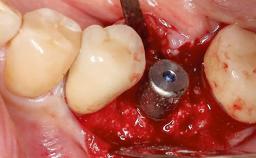

A 37-year-old male patient was referred to the Department of Periodontology at the University of Bern, Switzerland, by a private dentist. Tooth 21 had been lost due to trauma and had been replaced with an implant and a cemented single crown. The tapered-effect tissue-level implant had a diameter of 4.1 mm, a length of 12 mm, and a sandblasted and acid-etched (SLA) surface (Straumann Dental lmplant System; Institut Straumann AG, Basel, Switzerland). The metal-ceramic crown had been cemented permanently, leaving a submucosal gap between the implant shoulder and the crown margin. Absence of marginal bone loss apical to the polished transmucosal neck of the implant could be observed .